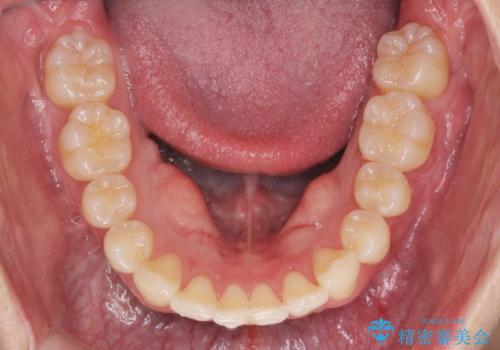

- 20代男性

- ワイヤー

- 10ヶ月

- 取り外しの必要なマウスピース矯正ではなくワイヤー矯正を希望され来院されました。

マウスピース矯正、ワイヤー矯正どちらの方法でも治療は可能ですが、ご要望の通りワイヤー矯正で歯の排列を行っていきます。